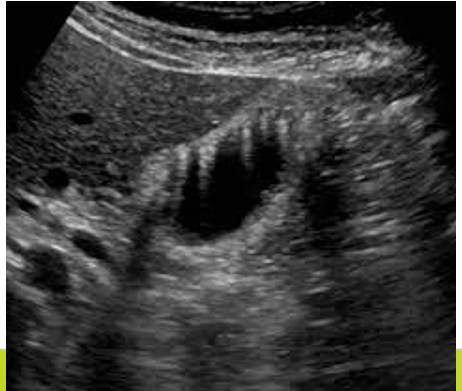

Comet Tail Artifacts

Multiple echoes from repeated reflections within a small but highly reflective object.

The artifact decreases in amplitude and width (tapers and fades) as it gets deeper.

Often seen with metal, crystalline materials.